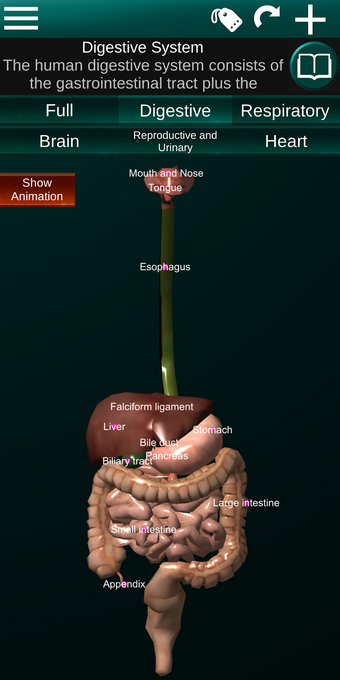

此应用程序显示人体器官的三维模型和所有器官的描述。

您可以触摸每个器官,如心脏、大脑、肺、生殖系统、肝脏、肠道、卵巢、睾丸、胃、肾脏等。

该应用程序旨在补充医学、生物学或其他领域的解剖学研究。

它对所有人都有用,甚至对学生也有用,因为每个解剖器官都以不同的颜色显示。

您可以使用该应用程序找出哪些是不同的身体器官以及它们的功能。